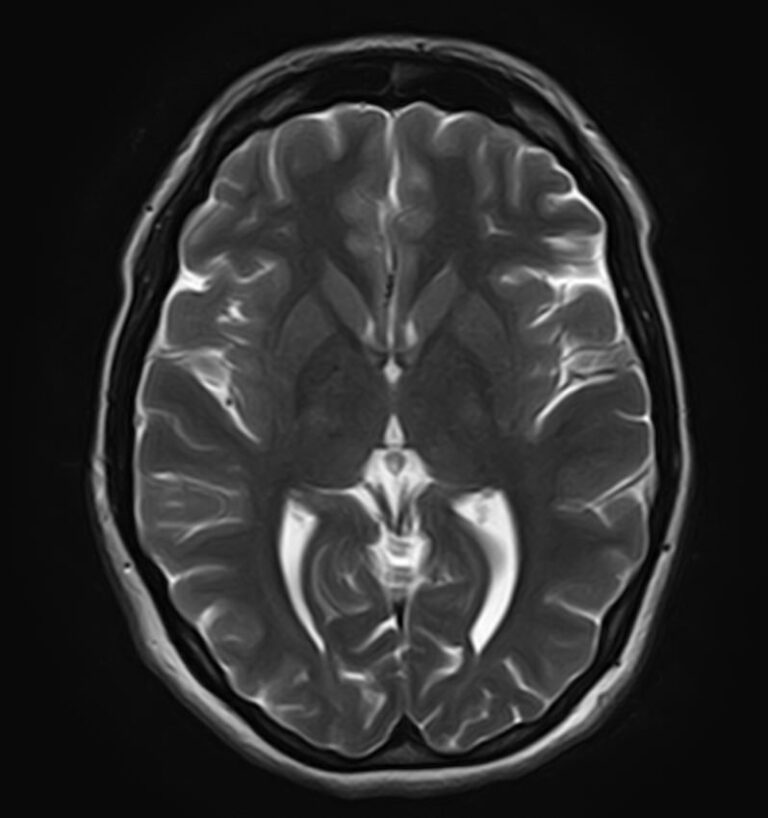

В клинике «Доступная медицина» можно пройти комплексное обследование, включающее в себя два протокола сканирования близко расположенных друг от друга анатомических областей – шейного отдела позвоночника и головного мозга.

Сканирование проводится на современном высокопольном магнитно-резонансном томографе закрытого типа TOSHIBA VANTAGE TITAN 1,5 Тесла, который делает послойные срезы в разных плоскостях с шагом от 1 мм и на основе полученных данных создает трехмерные изображения превосходного качества. Метод исследования позволяет в мельчайших подробностях визуализировать состояние всех структур головного мозга и шейного отдела позвоночника, что дает возможность выявлять патологические изменения на ранних стадиях и назначать своевременное лечение.